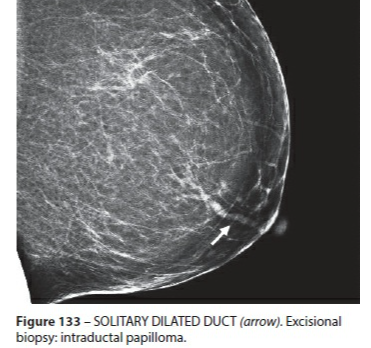

Ectasie Canlaire Solitaire

- Rare

ductal duct ectasia canal canalaire ectasiante

Ectasie Canlaire Solitaire

ductal duct ectasia canal canalaire ectasiante